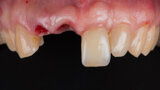

Immediate placement and restoration of a Straumann BLX implant replacing maxillary incisors